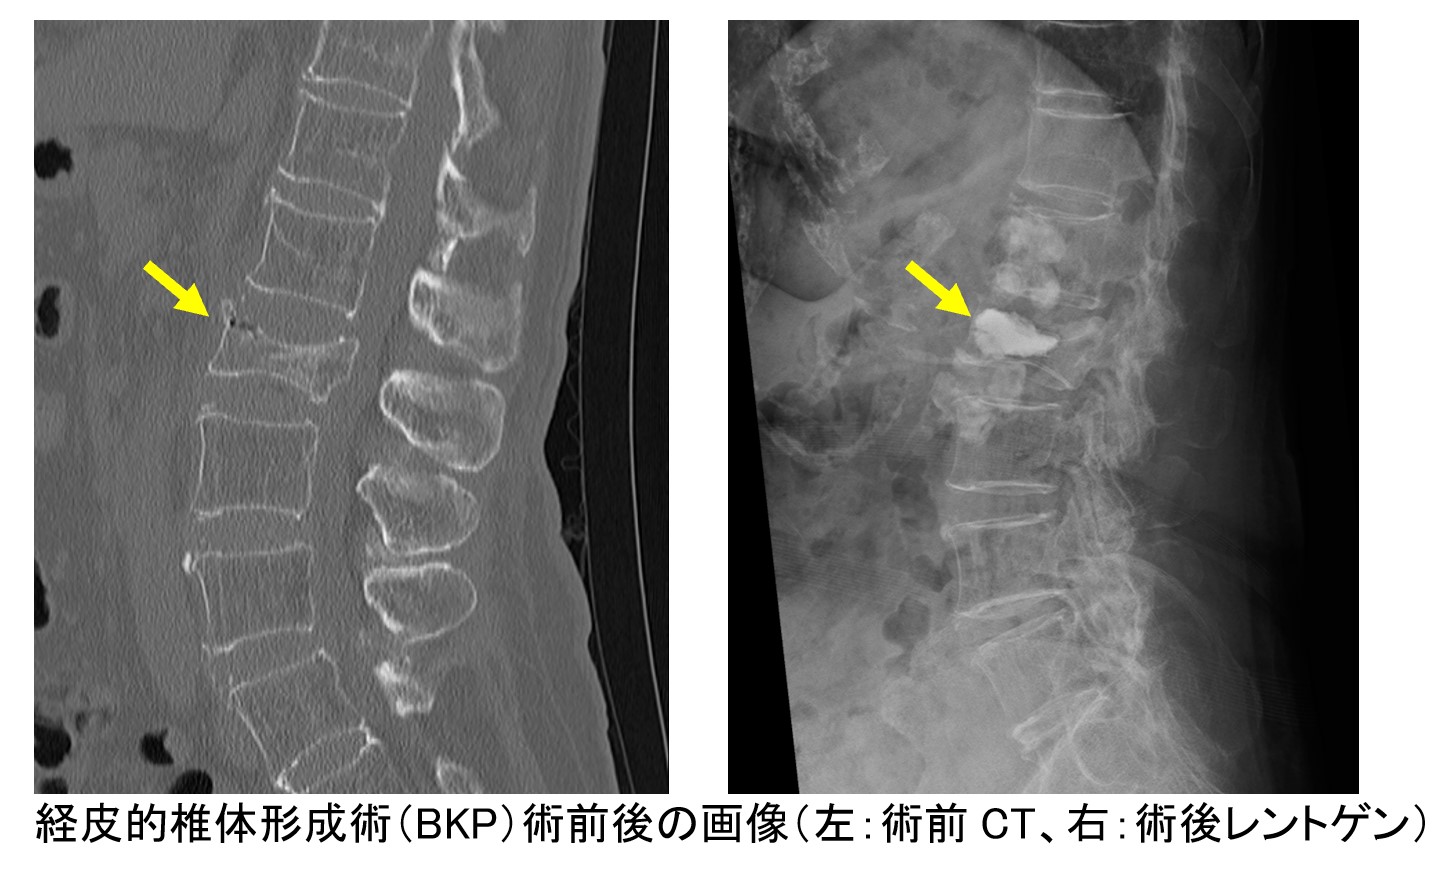

骨折の場所やタイプによっては、小さな傷から骨折部にセメントを注入することで骨折した椎体を安定化させる『経皮的椎体形成術(BKP・VBS)』を行うことがあります。しかしながら骨折により背骨の安定性が失われた場合や骨折によって神経が圧迫されている場合は、脊椎固定術が必要となります。その場合でも従来よりも小さな傷で極力背中の筋肉を温存することができる『最小侵襲脊椎安定術(MISt)』に積極的に取り組むことで、より安全で早期回復が期待できる手術を行うように心掛けています。